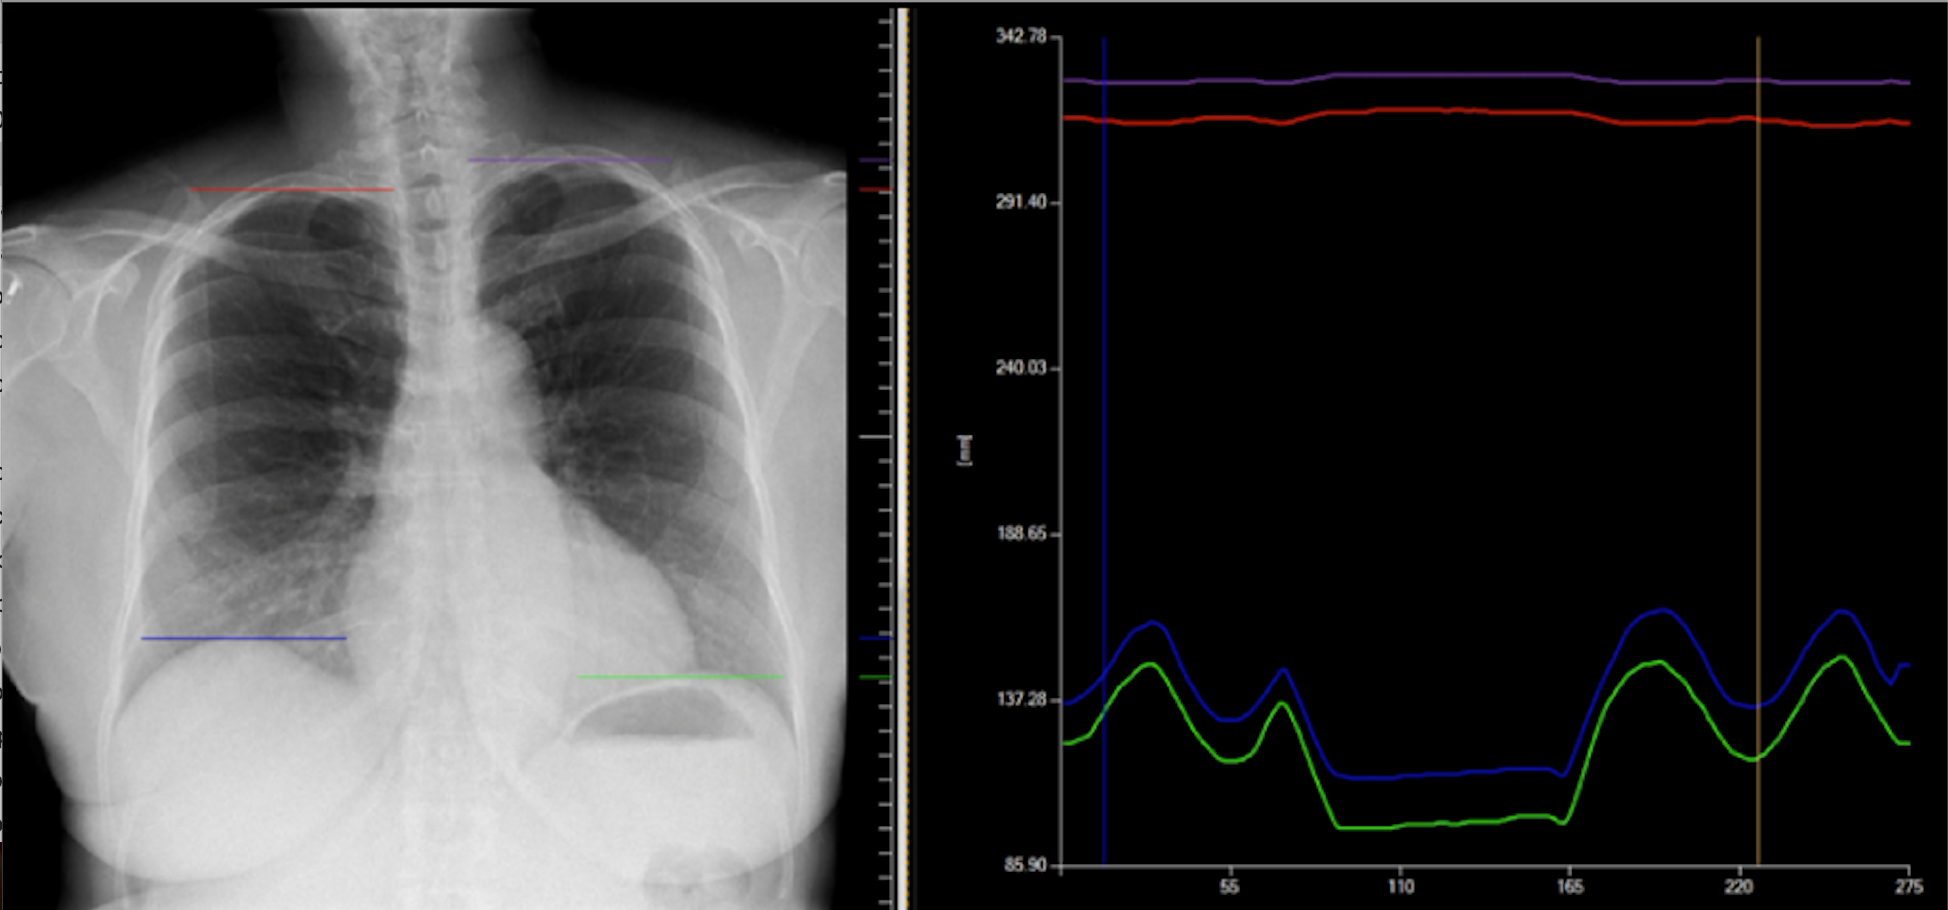

Portable Dynamic Digital Radiography Detects Airflow Impairment Following Lung Transplantation